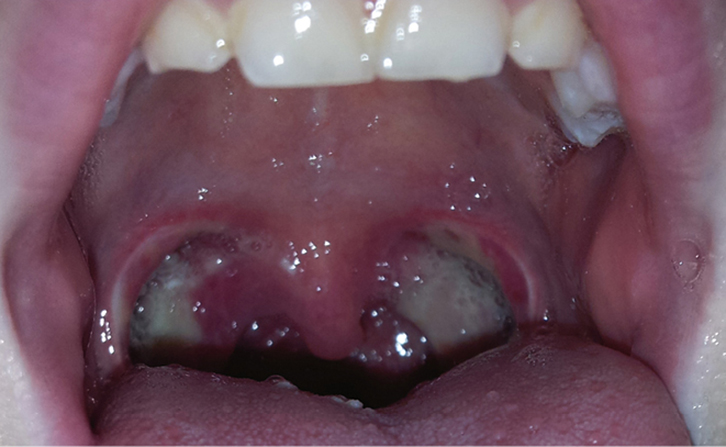

What does the oropharynx look like post operatively? The image below shows what we would expect to see in a normal throat at day 3 and day 10 post operatively.

Day 3